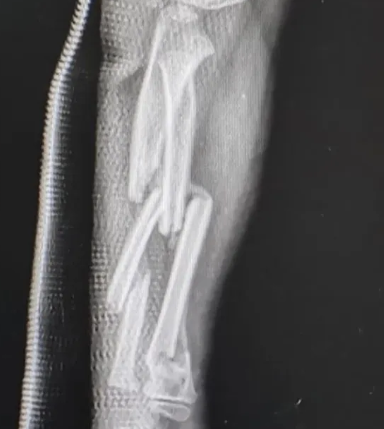

20岁的大学生小李和同学掰手腕,结果肱骨干螺旋形骨折,胳膊被固定休养了3个月。

图片来源:福建卫生报)